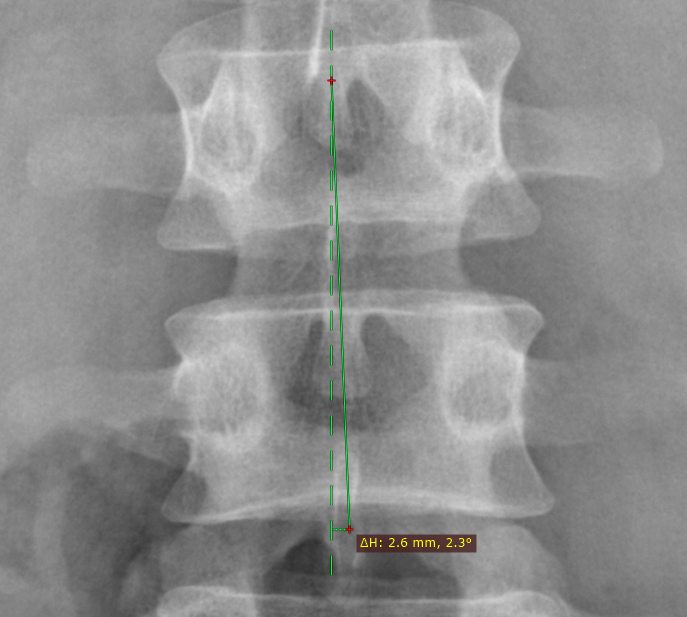

垂直偏差测量

将显示两个测量值:

• 线段一端到与另一端相交的水平线(或垂直线)之间的垂直(或水平)距离(毫米)

• 线段与该水平线(或垂直线)之间的夹角(度)